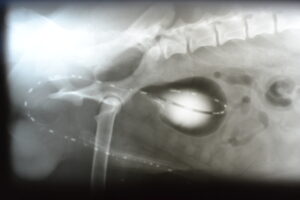

Kontrastní vyšetření močového měchýře